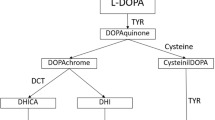

Oculocutaneous albinism type 1 (OCA1, OMIM 203100) is produced by mutations in the tyrosinase gene on chromosome 11q (Tomita et al. 1989; Spritz et al. 1990; Oetting and King 1999). Mutations in this gene produce the classic picture of life-long white hair and skin, and blue eyes with translucent irides, a phenotype that has been described in most ethnic groups worldwide and recognized throughout human history (Pearson et al. 1911). This form is known as OCA1A and results from tyrosinase gene mutations that produce no enzyme (Schnur et al. 1996) or inactive enzyme (Tripathi et al. 1992; Halaban et al. 2000; Toyofuku et al. 2001). Many individuals with OCA1 do not have this phenotype, however, but rather have variable amounts of hair and skin pigment (King et al. 1991; Giebel et al. 1991a, 1991b; Matsunaga et al. 1999; Passmore et al. 1999). This form is known as OCA1B, and the phenotype can vary from minimal to nearly normal cutaneous and hair pigment in adult life and can overlap with the phenotypes resulting from mutations in other OCA-related genes. We now report our analysis of the tyrosinase gene in a large group of individuals who meet clinical criteria proposed for OCA1, in order (1) to determine whether accurate clinical criteria for tyrosinase-related OCA can be developed, and (2) to characterize the associated mutations.